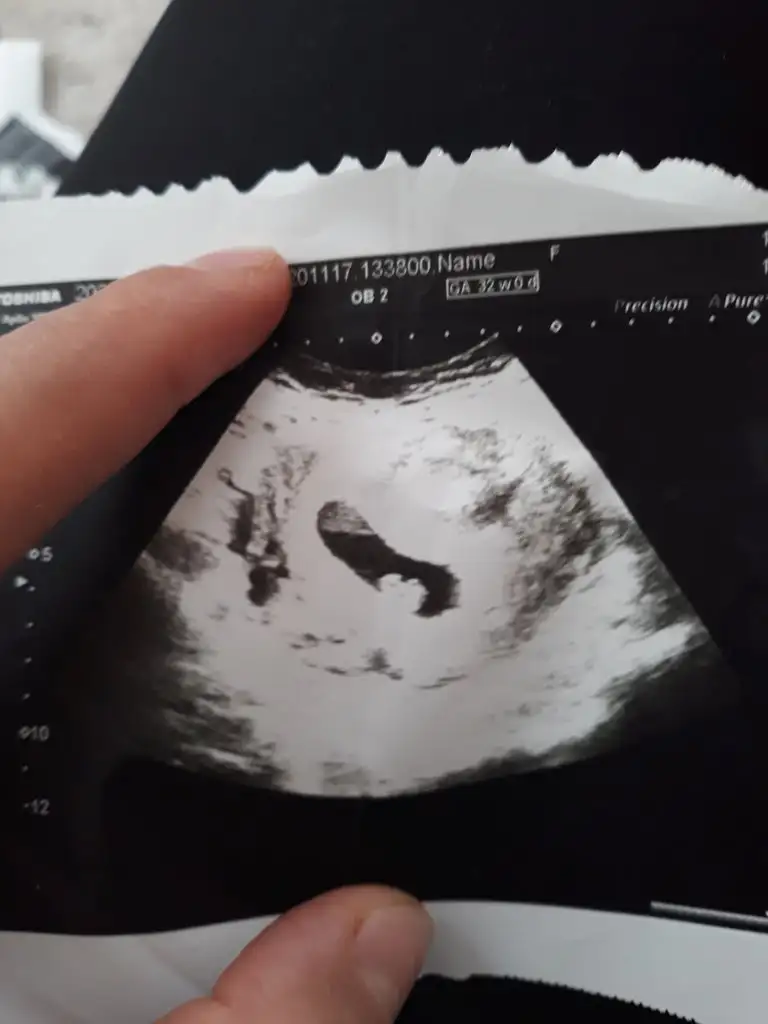

Ramzi Teorisi ve cinsiyet tahmini ( tutma olasılığı %85 miş )

Benim bebiş te 6+6iken karından Ultrason sizin tahmininiz nedir kızlar